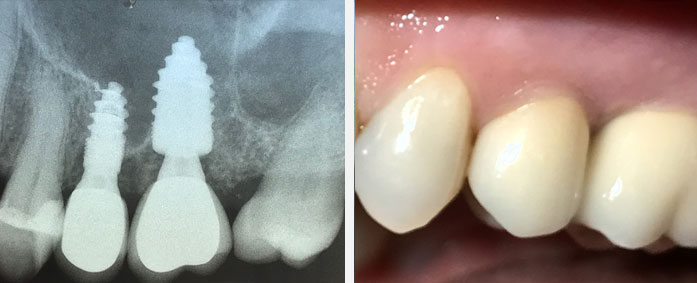

Bei Implantaten handelt es sich um künstliche Zahnwurzeln, die operativ in den Kieferknochen eingebracht werden. Nach einer gewissen Einheilzeit wird auf den Implantaten der neue Zahnersatz sicher getragen.

Mit Hilfe unseres Implantatsystems, sind wir in der Lage, Implantate minimalinvasiv – das heißt, ohne Auf-

schneiden und wieder Zunähen des Zahnfleischs – schmerzarm einzusetzen. Zusätzlich sind Knochenauf-

bauoperationen, wie sie bei anderen Systemen oftmals notwendig sind, nahezu überflüssig.